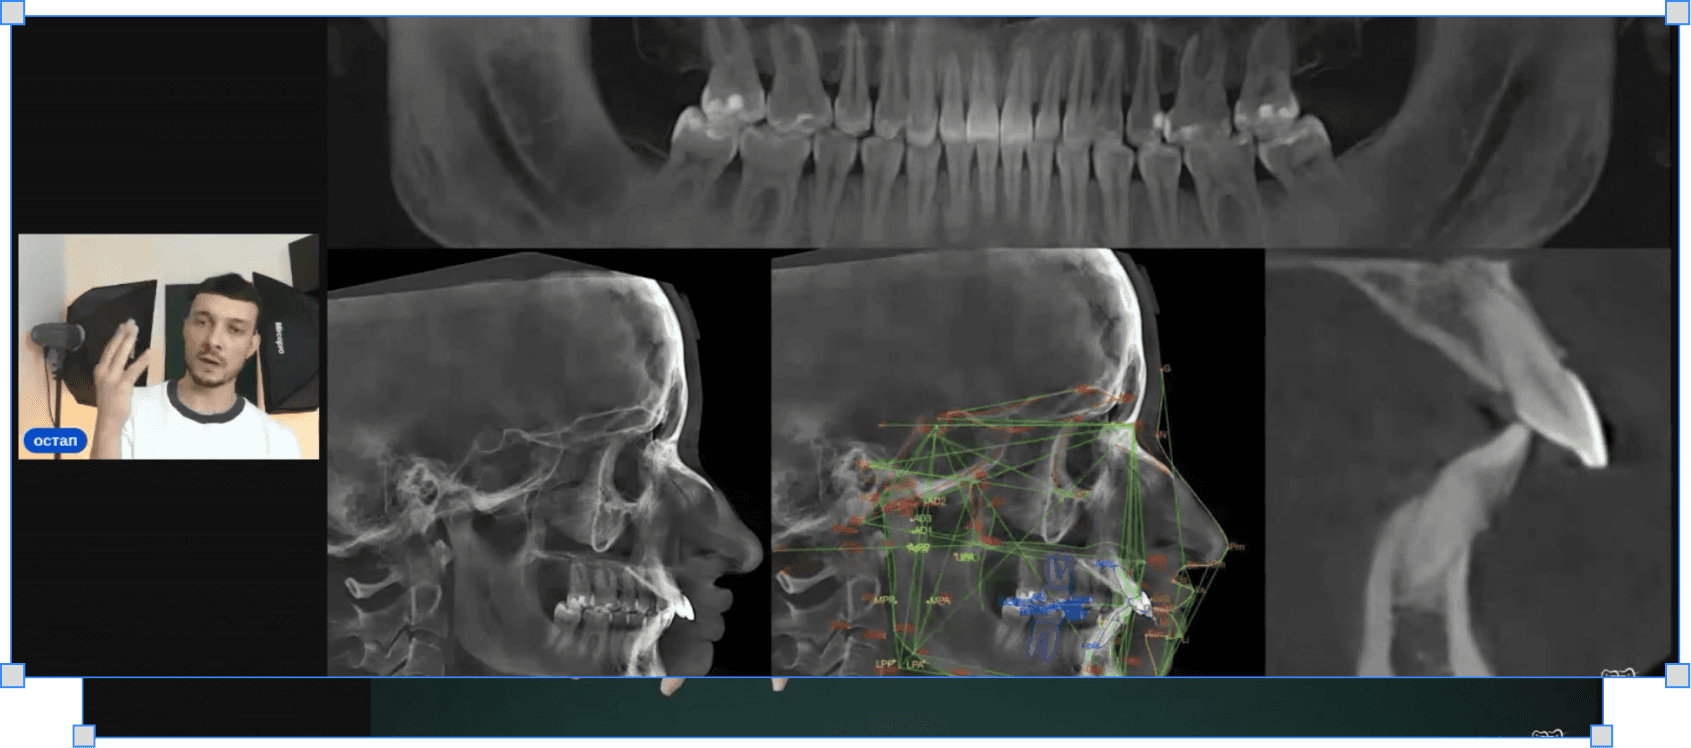

Як діагностувати другий клас для видалення

Фотографії, аналіз скученості і трем — що дивитись і в якому порядку до будь-якого рішення

Як визначити таймінг і вибір видалення

Коли видаляти, коли чекати і що змінюється залежно від стану кістки

Як асиметрично видаляти премоляри верхнього ряду

Логіка вибору — четвірка чи п'ятірка, з якого боку і чому це не завжди симетрично